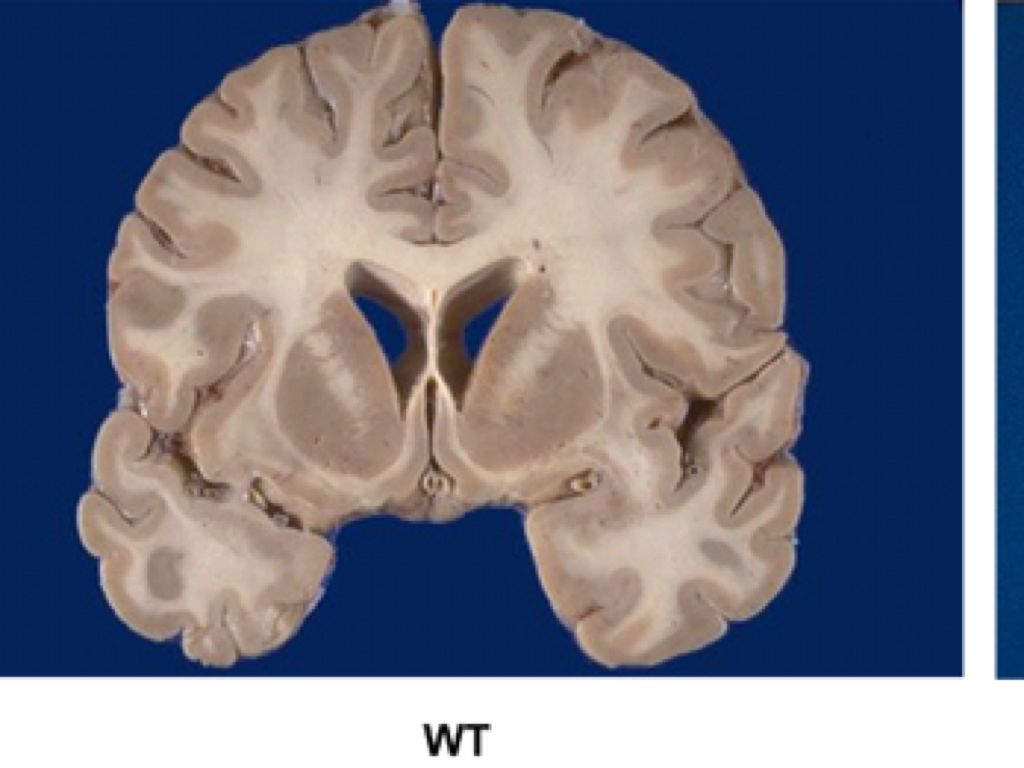

WHAT IT IS

Huntingtons disease/Huntington's chorea is when mutated genes are programmed to degenerate nerve cells in the brain.